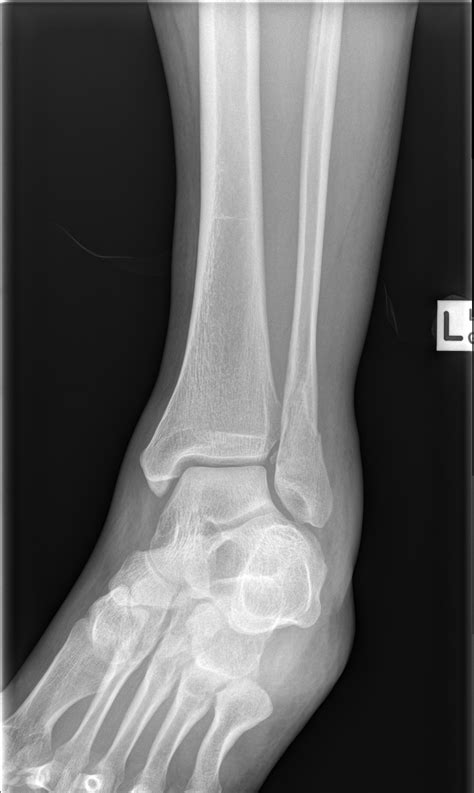

Diagnosis of Proximal Fibula Fracture

Diagnosing a Proximal Fibula Fracture involves a combination of physical examination and imaging tests. The diagnostic process typically includes:

• Physical examination: A healthcare provider will assess the injured area for pain, swelling, and deformity.

• X-rays: Imaging tests to visualize the bone and determine the location and severity of the fracture.

• CT scans or MRI: In some cases, more detailed imaging may be required to assess the extent of the injury and plan treatment.